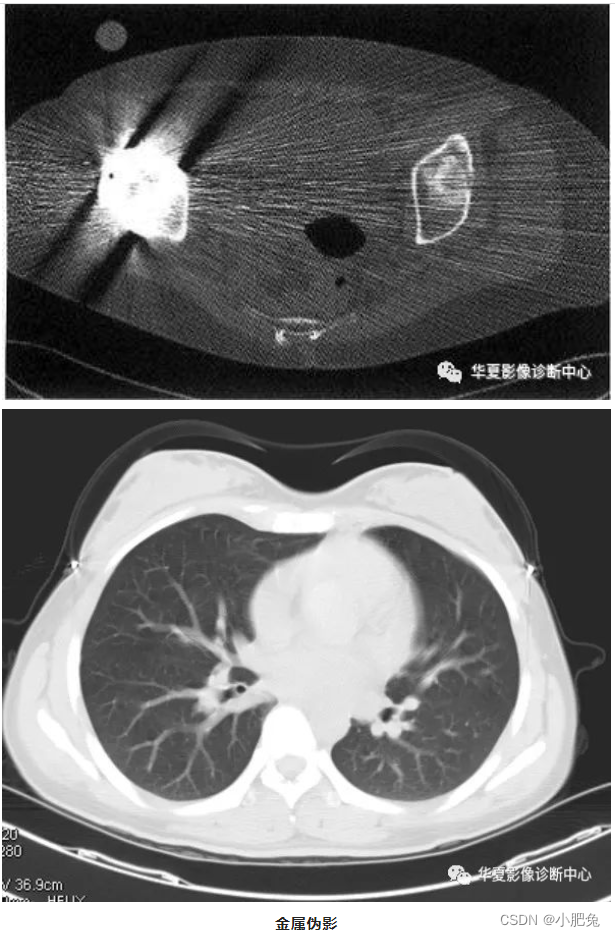

二、金属伪影

患者身上携带的金属物质, 如耳环、 项链、 硬币 、 钥匙和电子器件等, 其他如患者体内的金属物质有假牙或牙内填充物、 外科手术缝合夹 、 节育环和心脏起搏器等对X射线的吸收作用, 使投影数据产生不完全, 这部分数据丧失结果产生典型的放射状条形伪影。

金属伪影避免的方法是:对患者携带的金属物可在扫描前去除 , 无法取下的假牙可设法采用倾斜机架角度避开。另外也可利用CT机上的金属伪影抑制软件改善图像质量 , 去除金属伪影软件的主要原理是采用遗失数据内插方法, 使由于金属物质对射线的衰减吸收造成的遗失数据,由操作者选择兴趣区, 然后在兴趣区部位通过数据的内插, 使结果的图像去除金属伪影。